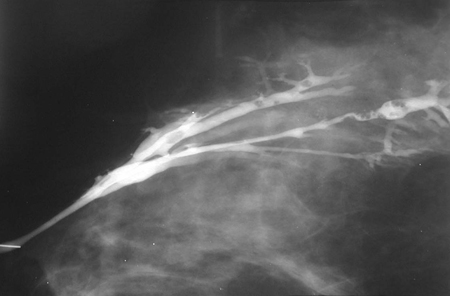

Ductograma en el que se observan múltiples papilomas intraductales

Cortesía de la Dra. Nancy Pile, University of Louisville; utilizada con autorización

Ver esta imagen en el contexto de la/s siguiente/s sección/es:

Evaluación de masas en la mama